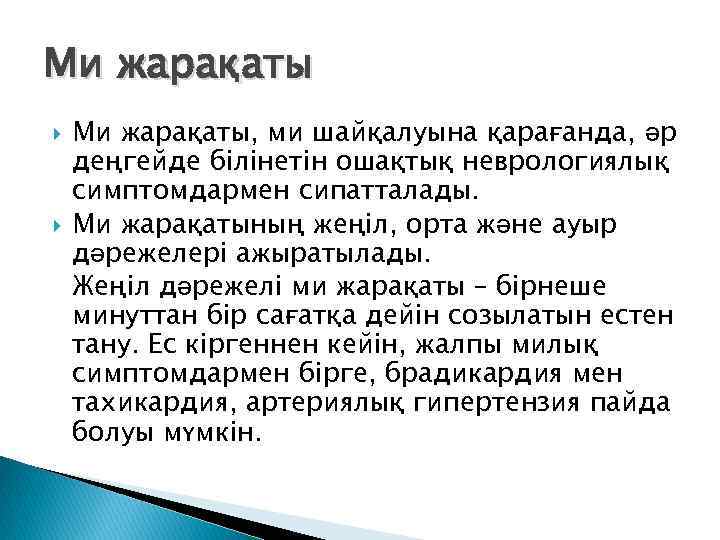

Ми жарақаты Ми жарақаты, ми шайқалуына қарағанда, әр деңгейде білінетін ошақтық неврологиялық симптомдармен сипатталады. Ми жарақатының жеңіл, орта және ауыр дәрежелері ажыратылады. Жеңіл дәрежелі ми жарақаты – бірнеше минуттан бір сағатқа дейін созылатын естен тану. Ес кіргеннен кейін, жалпы милық симптомдармен бірге, брадикардия мен тахикардия, артериялық гипертензия пайда болуы мүмкін.